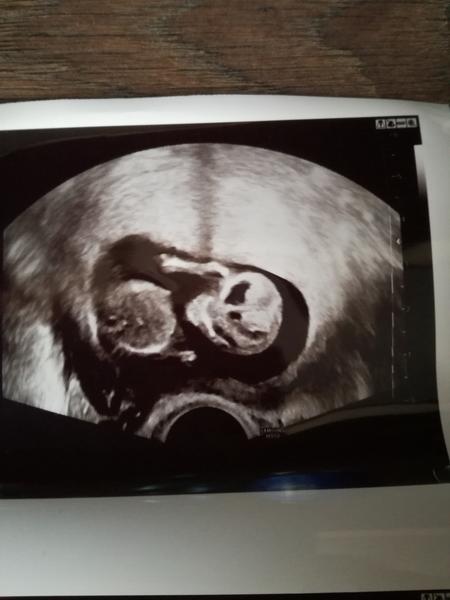

Ahojte babule ,tak prikladam tak ako som slubila ... Dnes 12+2 ...